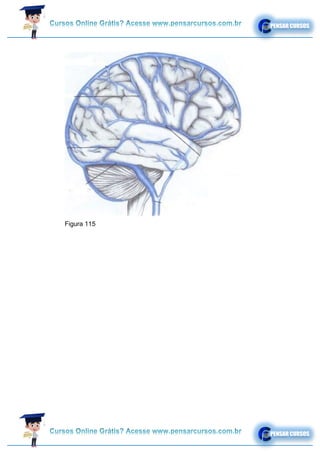

Figura 113

Figura 115